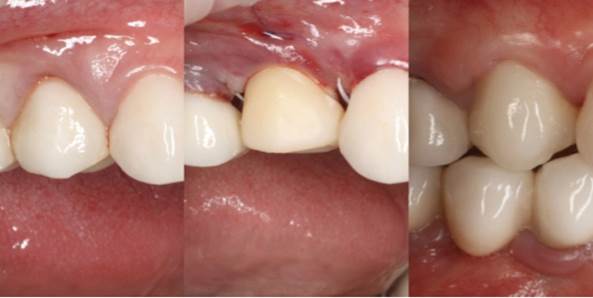

Clinical case: AnyRidge immediate loading

- Courtesy of Dr. Andres Paraud Freixas, Chile -

AnyRidge, ISQ value, initial stability, immediate loading, KnifeThread, maxillary anterior, Mega ISQ, Dr. Andres Paraud Freixas

“Patient’s smile was recovered on the day of surgery

with reliable & highly-aesthetic results using AnyRidge & R2GATE. ”